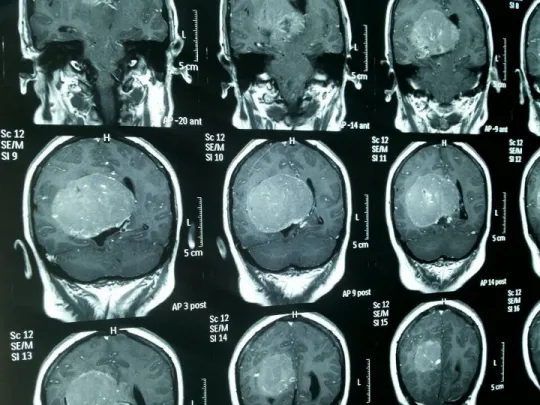

2014年,她在双目失明2个月后,终于接受了右侧侧脑室三角区巨大肿瘤切除手术,此时肿瘤大小达8.3cmx7.2cm,为良性脑膜瘤。

影像资料:当时肿瘤已长得很大